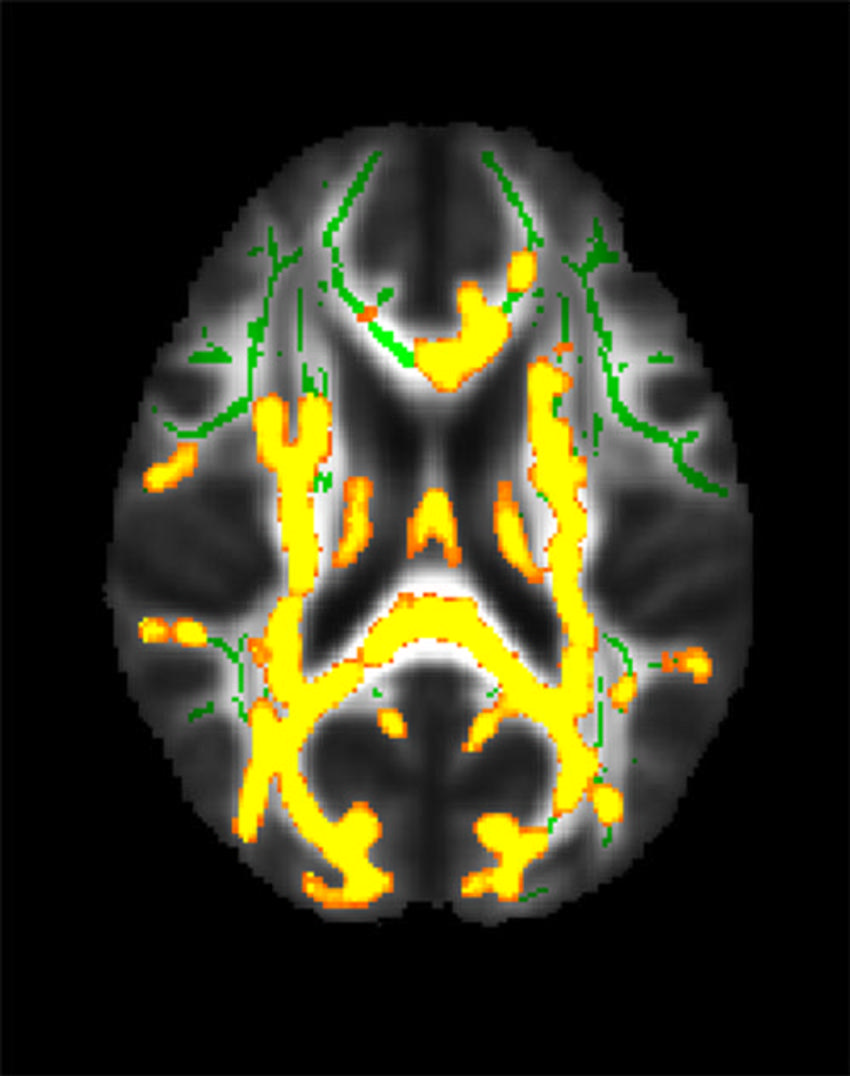

The researchers found that a higher visceral to subcutaneous fat ratio was associated with higher amyloid PET tracer uptake in the precuneus cortex, the region known to be affected early by amyloid pathology in Alzheimer's disease. This relationship was worse in men than in women. The researchers also found that higher visceral fat measurements are related to an increased burden of inflammation in the brain.

Figure 1. This figure shows increased neuroinflammation (yellow colors) associated with higher hidden fat (visceral fat) in the cohort of 54 participants with an average age of 50 years in the brain’s white matter. The green colors are the normal white matter.